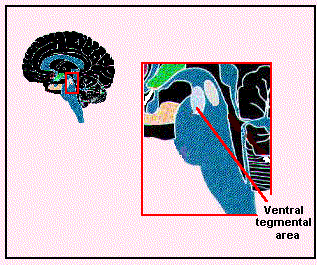

Am Aufbau unserer freudigen Erwartungen, Vorfreude, inneren Antriebs (Motivation), Freude, „allem was uns gut tut“ und Glücksgefühle (sowie allen legalen Genussmitteln, allen Verhaltenssüchten wie die zur Zeit topaktuelle Spielsucht und allen illegalen Drogen und Süchten) sind also beteiligt:

Ventral tegmentales ArealEine Hirnregion, die von Fachärzten, Hirnforschern und Kennern der Materie – wegen ihrer Lage im bauchwärts (anat.: ventral) liegenden Bereich des Hirnstamms – ventral tegmentales Areal (VTA) genannt wird. Sie ist das A und Ω und der Ursprungsort des Lust-, Belohnungs- und Glückssystems. Im VTA beginnt und endet es nach Rückmeldungen von Partnerzellen im Mittel- und Vorderhirn:

Zwei funktionelle Magnetresonanz-Tomografie-Aufnahmen vom VTA, © Kimberlee D'Ardenne, Science, 2008